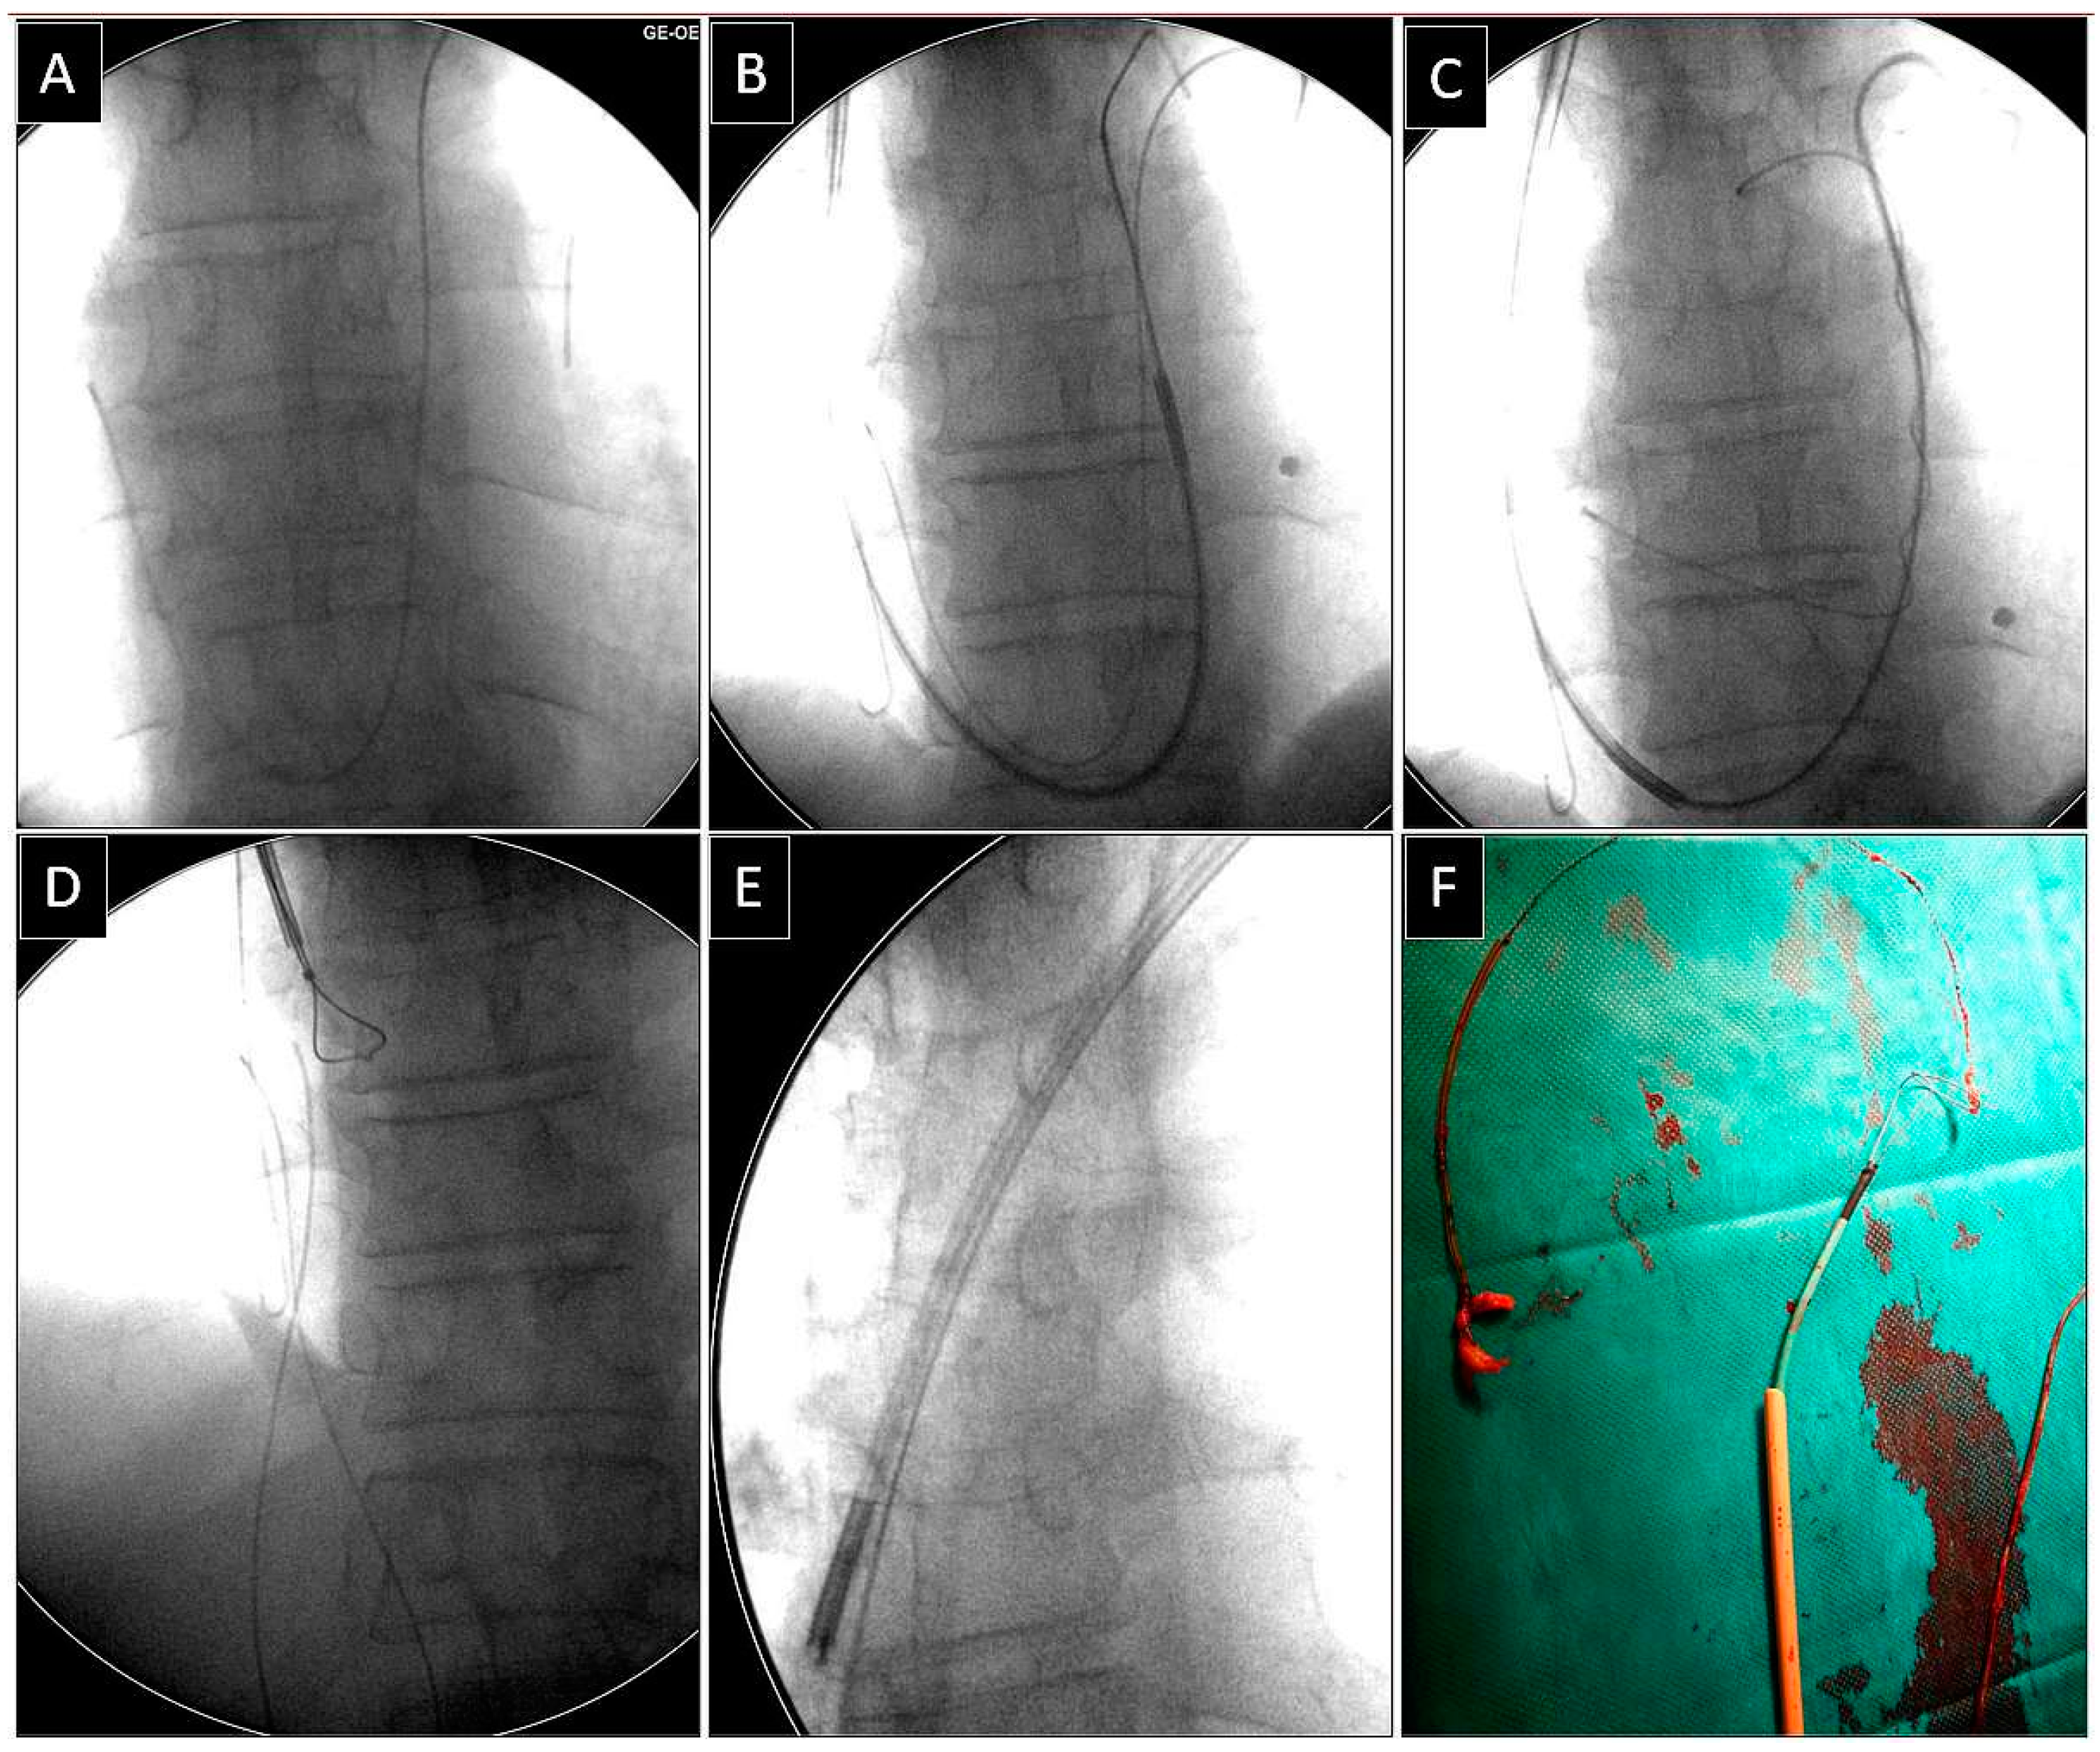

Extraction of Leads with Migrated Proximal Ends into the Cardiovascular Space

- Removal of such leads requires the use of different approaches and dedicated and non-dedicated tools.

| Superior approach | 6 (15.39) | 3 (23.08) p = 0.832 | 3 (23.08) p = 0.832 | 5 (71.43) p = 0.007 | 17 (23.61) |

| Lasso/basket in CS sheath and a polypropylene or rotational sheath over them (dilatation) | 13 (76.47) | Lasso/basket in CS sheath and a polypropylene rotational sheath over them—superior approach (dilatation) | 8 (100.0) |

| Lasso/basket in CS sheath—superior (pulling only) | 1 (5.88) | Lasso/basket in CS sheath—superior approach (pulling only) | 0 (0.00) |

| Lasso/basket only (pulling only) | 3 (17.65) | Lasso/basket only—superior approach (pulling only) | 0 (0.00) |

| Loop (pulling, end release) | 6 (35.29) | Loop femoral approach | 6 (75.00) |

| Pig-tail + winding and shifting superior approach (end release) | 3 (17.65) | Pig-tail femoral approach | 1 (12.50) |

| Pig-tail superior (end orientation) | 0 (0.00) | Pig-tail + winding and shifting femoral approach | 1 (12.50) |

| Risk of MC-TLE procedure interrupted | 1 (1.39) | Loop femoral approach (pulling, end release) | 42 (58.33) |

| Haemopericardium—rescue cardiac surgery | 1 (1.39) | Loop superior approach (pulling, end release) | 6 (8.33) |

| All: | 2 (2.28) | Pig-tail + winding and shifting femoral approach (pulling, end release) | 8 (11.11) |

| Pig-tail + winding and shifting superior (pulling, end release) | 3 (4.17) | ||